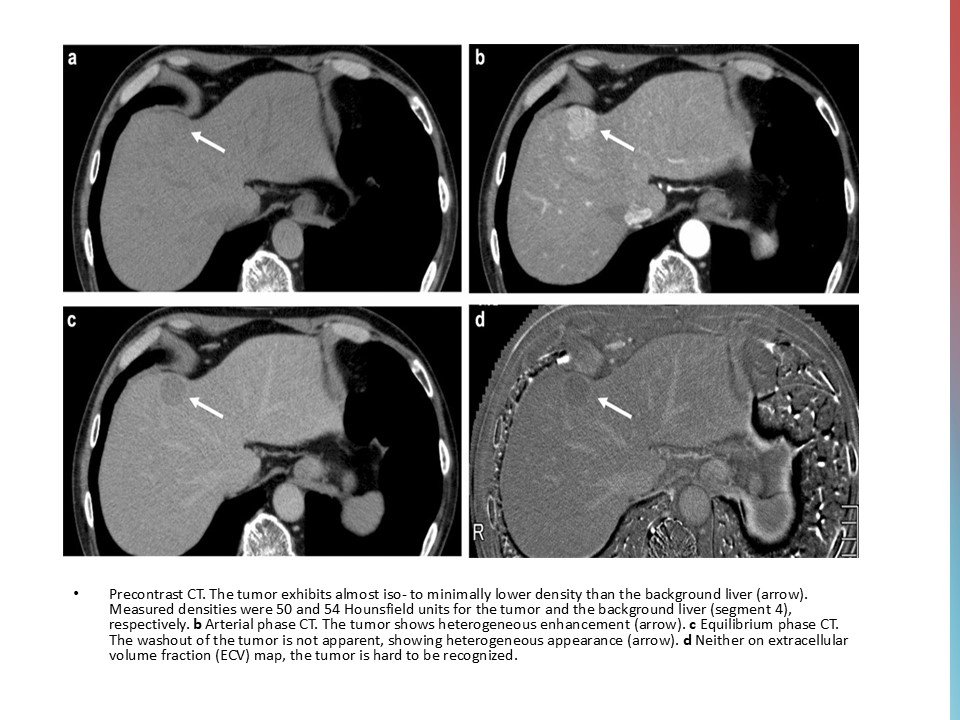

CT and MR images in a 37-year-old male with poorly-differentiated HCC with histological capsule. METAVIR score of the background liver was F3. In contrast-enhanced CT, a 49-mm observation shows (a) nonrim APHE on arterial phase and (b) nonperipheral washout with an enhancing capsule on equilibrium phase. In gadoxetic acid-enhanced MRI, a 48-mm observation shows (c) nonrim APHE on arterial phase, (d) nonperipheral washout on portal venous phase, and (e) TP hypointensity with suspicion of an enhancing capsule on transitional phase. Hepatobiliary phase image clearly shows (f) a nonenhancing capsule surrounding the observation.